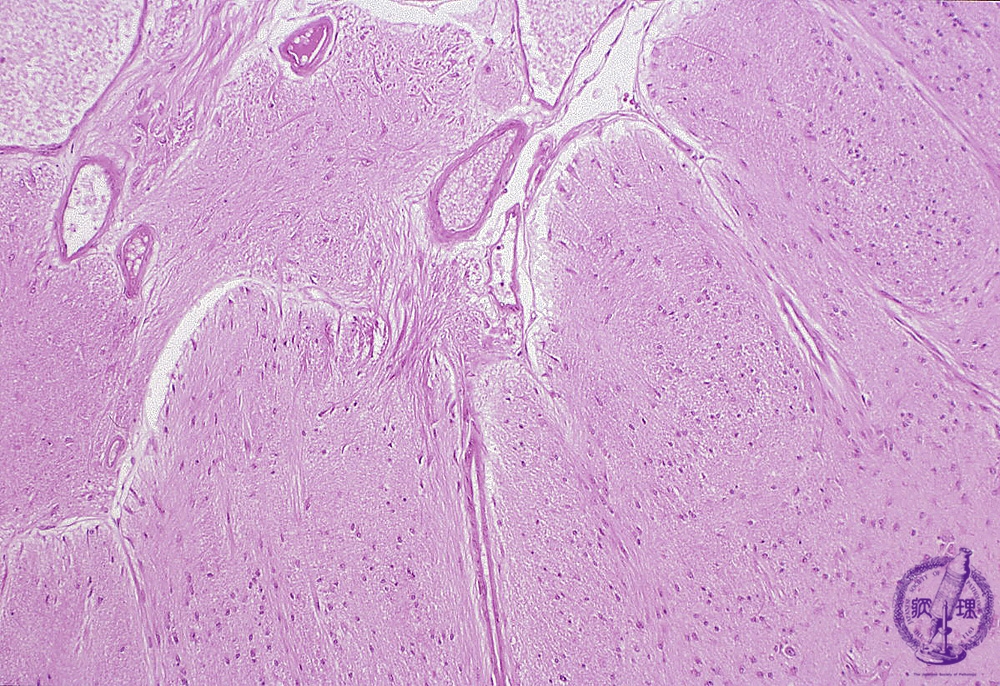

- (8)Glioma(Astrocytoma)

Microscopic findings (H.E. low magnification): Fibrillary astrocytoma demonstrated a diffuse proliferation of tumor cells with small oval nuclei and fine neurites. Nuclear polymorphism was not prominent. Tumor cells invaded the subarachnoidal space in left upper of the figure.